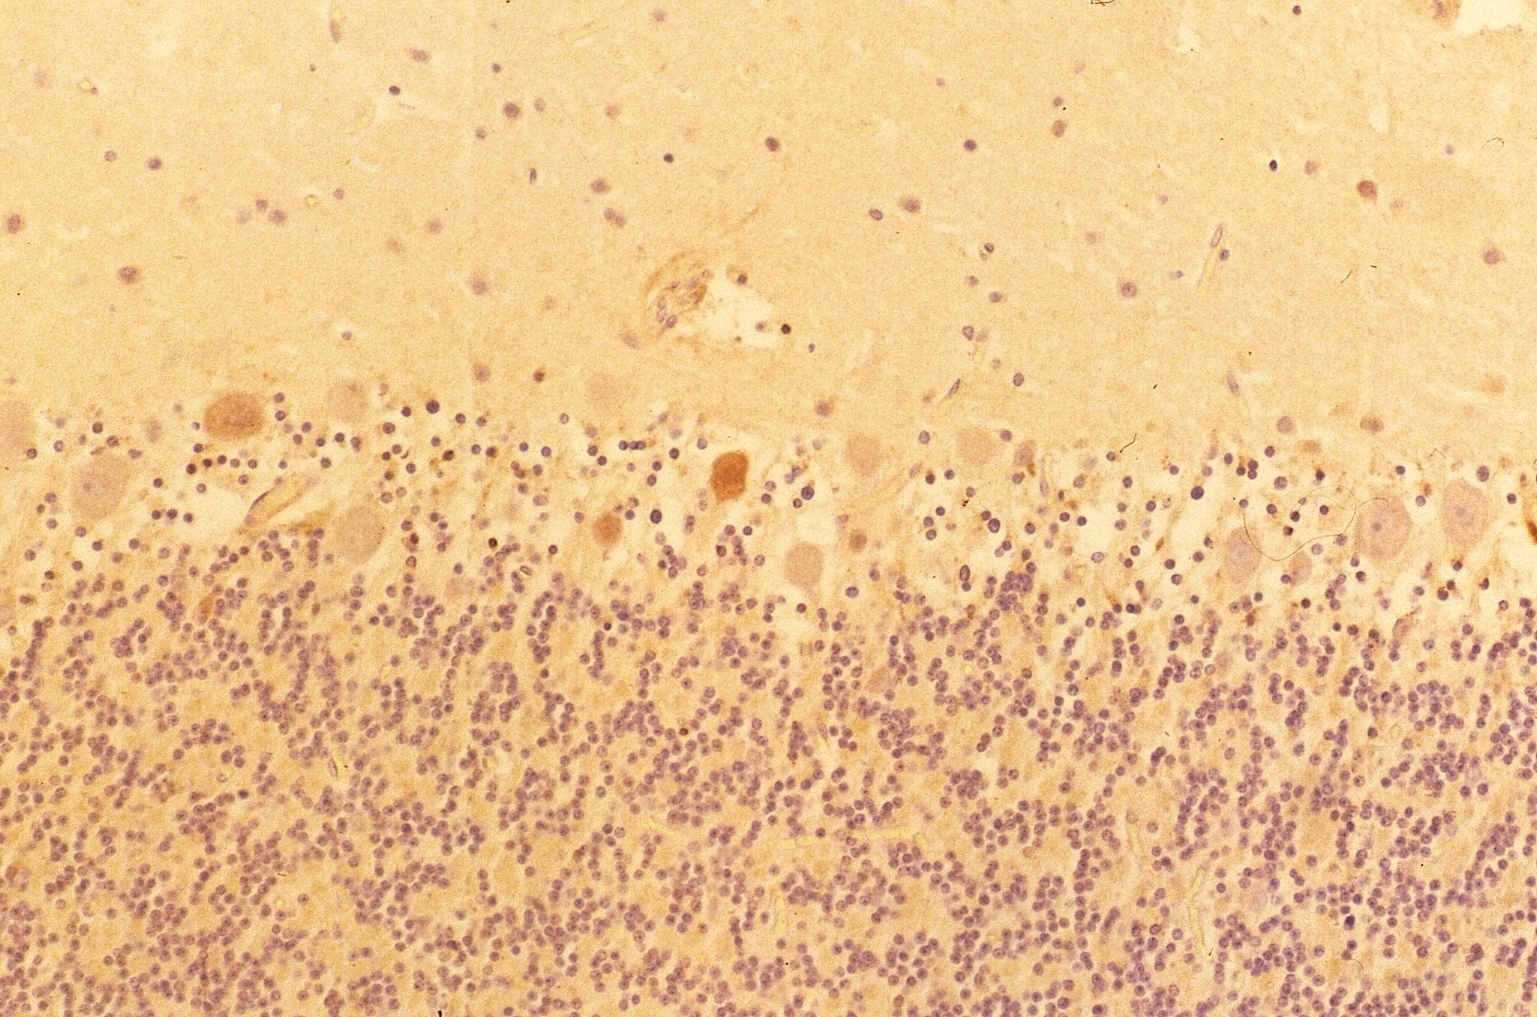

The Purkinje cells and the neuronal cells in the dentate nucleus (data not shown) in the cerebellum were clearly and intensively stained by the antibody (Fig. 3), although small amount of the Purkinje cells showed feeble or no reactivity with the antibody. The reactivity with anti-PGDS with the Purkinje cells was variable.

Fig. 3

Immunostaining (DAB) of anti-PGDS antibody in cerebellum

(a)                                       (b)

Fig . 5

Figure 5 shows a case of DAB staining with anti-PGDS antibody in cerebellum. This individual had suffered from acute ischemia, falling unconscious and been in vegetative state for months before he passed away. The granular layer and molecular layer were loosely attached along Purkinje cells. There are some Purkinje cells visible but only one showed positive reaction to the anti-PGDS antibody (left in Fig. 5). And two cells showed condensed staining of anti-PGDS antibody (middle in Fig.5). Other Purkinje cells show no reactivity to anti-PGDS antibody. We think this was due to the brain damage followed by ischemia and hypoxia and the cell with the condensed staining may be undergoing/have undergone the apoptotic changes through the period of the vegetative state. Although this was the known history of hypoxia, we can also determine whether or not there was a brain damage in cases with suspected hypoxia.